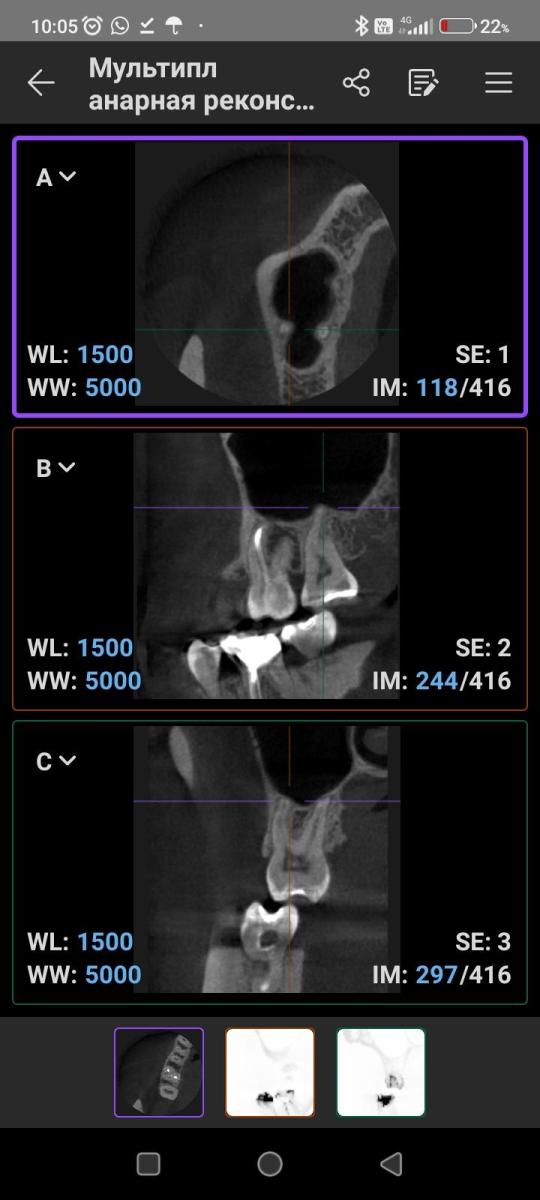

Что может означать затемнение на верхушке корней 17 зуба? Есть ли дентикли в пульпе? Есть постоянная не острая болезненность по ходу верхнечелюстной ветви. Может ли источником боли быть 17 зуб?

"Что может означать затемнение на верхушке корней 17 зуба?"

"Есть ли дентикли в пульпе?"

"Может ли источником боли быть 17 зуб?"